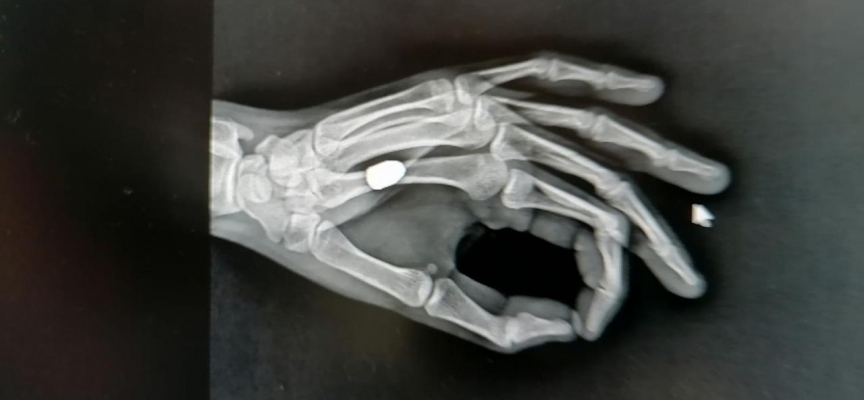

Tedaviye alınan İskender'e çekilen röntgende, avucuna yorgun merminin saplandığı tespit edildi. Mermi çekirdeği elinden ameliyatla alınan İskender, taburcu edildi. Polis ekipleri, olayla ilgili inceleme başlattı.

Sürmene Devlet Hastanesi Başhekimi Osman Yoloğlu, röntgen filminde mermi tespit ettiklerini belirterek, "Elinde ağrı hissettiğini söyleyen hastamızın elinde de bir yarası vardı. Yaptığımız tetkikler sonrası elinde, mermi çekirdeği olduğunu tespit ettik. Hastamızı hemen ameliyata aldık ve elinden mermi çekirdeğini çıkarttık. Durumu, çok şükür iyi” diye konuştu.